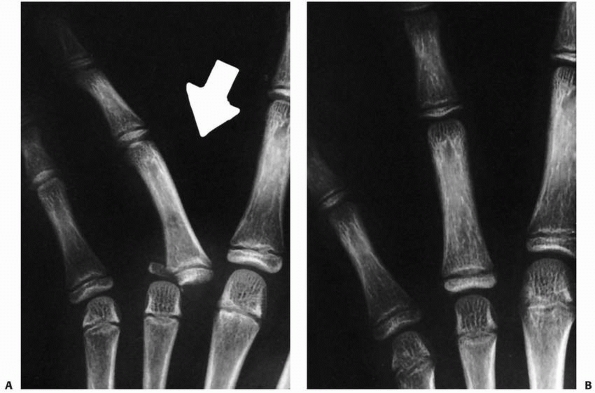

Displaced fractures often require closed reduction. A common fracture

pattern is a S-H II fracture along the ulnar aspect of

the

proximal phalanx of the small digit. The small digit is angulated in an

ulnar direction. This fracture has been termed the “extra-octave

fracture” to denote its potential benefit to the span of a pianist’s

hand (Fig. 8-29).153

Minimal displacement is treated with splinting in the safe position for

3 weeks. Moderate displacement requires closed reduction with local

anesthesia or conscious sedation. Placing the MCP joint into flexion to

tighten the collateral ligaments and angulating the digit into radial

deviation reduces the fracture. Placing a pencil or digit in the web

space and using it as a fulcrum to assist reduction has been

recommended.207 Minimal force is necessary to restore alignment.5,51 Buddy taping and cast immobilization will maintain alignment until healing.